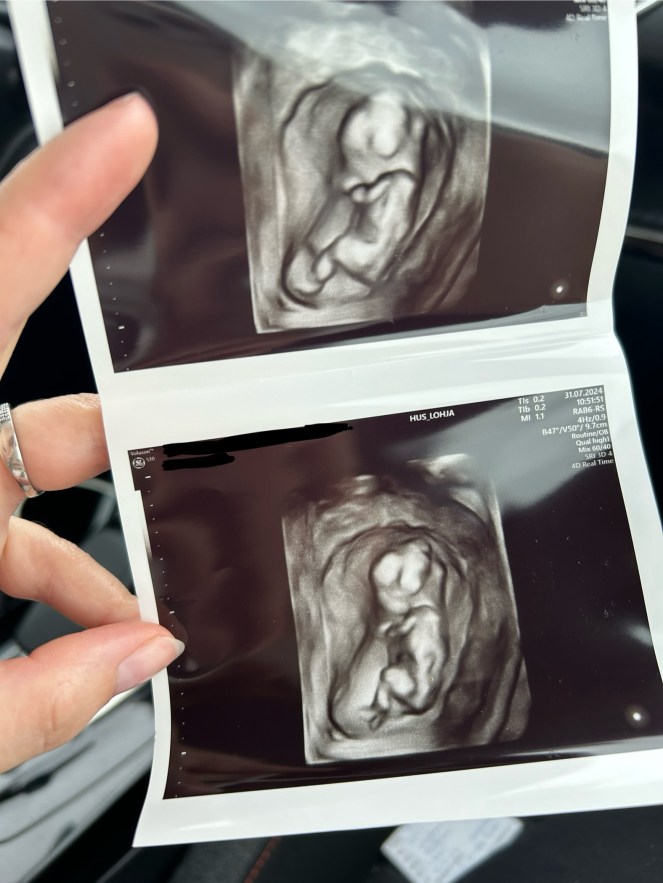

Jäin kesälomalle raskausviikolla 12 ja pääsimme käymään Lohjan sairaalassa varhaisraskauden ultraäänitutkimuksessa, jossa tarkasteltiin lähemmin mm. vauvan kokoa ja rakennetta sekä istukan sijaintia. Normaalisti tämä on raskauden ensimmäinen ultraäänitutkimus, mutta me olimme jo ehtineet käydä Tilkassa IVF-hoitojen jälkeisessä ultrassa viikolla 7. Tässä vaiheessa vauva näytti kuitenkin jo ihan oikealta vauvalta ja hetki oli merkityksellinen monella tavalla. Saimme kuulla että vauva on terve eikä ultrassa havaittu minkäänlaisia poikkeavuuksia. Heti siitä hetkestä alkaen kun näin ruudulta pienen vauvamme aloin itkeä eikä siitä meinannut tulla loppua. Se taisi olla ensimmäinen kerta kun oikeasti sisäistin sen, että tästä raskaudesta voisikin saada toivotun lopputuloksen. Sisälle rakentamani pato murtui ja itkin vihdoin pois kaikki ne lapsettomuuden aiheuttamat kivut ja pelot. Olo oli sen jälkeen niin onnellinen ja kevyt.